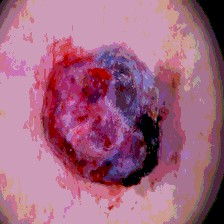

Timely identification and treatment of rapidly progressing skin cancers can significantly contribute to the preservation of patients' health and well-being. Dermoscopy, a dependable and accessible tool, plays a pivotal role in the initial stages of skin cancer detection. Consequently, the effective processing of digital dermoscopy images holds significant importance in elevating the accuracy of skin cancer diagnoses. Multilevel thresholding is a key tool in medical imaging that extracts objects within the image to facilitate its analysis. In this paper, an enhanced version of the Mud Ring Algorithm hybridized with the Whale Optimization Algorithm, named WMRA, is proposed. The proposed approach utilizes bubble-net attack and mud ring strategy to overcome stagnation in local optima and obtain optimal thresholds. The experimental results show that WMRA is powerful against a cluster of recent methods in terms of fitness, Peak Signal to Noise Ratio (PSNR), and Mean Square Error (MSE).